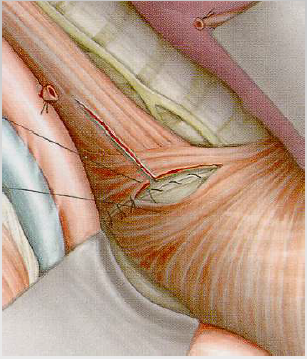

Divertikulektomiya və miotomiya

Ən radikal müalicə üsuludur. Divertikul boyun nahiyəsindən kəsilir, atılır və miotomiya edilir. 90% hallarda nəticə qənaətbəxş olur.

- Divertikulektomiya

- Miotomiya – divertikulun əks tərəfindən aparılır. Kəsik divertikulun boyunu səviyyəsindən başlanılır və mədəyə doğru 2 sm uzadılır.

- Hissəvi fundoplikasiya reflüksü önləmək üçün icra edilir.